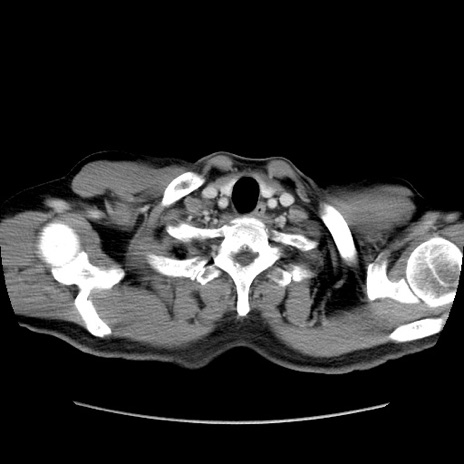

症例34(横断像)

【症例】60歳代 男性

【主訴】右鼠径部膨隆

【現病歴】1年程前より右鼠径部膨隆あり。自己にて還納可能だったため放置していた。3時間前より右鼠径部の脱出を認め、還納困難となり受診。

【既往歴】高血圧

【身体所見】右鼠径部に小児頭大の膨隆あり。弾性硬であり、用手還納は困難。左鼠径部にも膨隆を認める。脱出はなし。

【データ】WBC 15500、CRP 測定なし